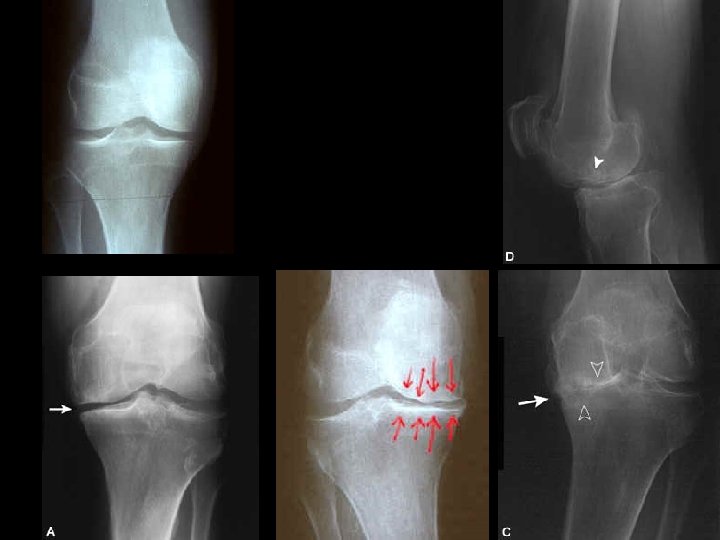

ASSESSMENT • For many plain radiograph remains the best means of assessment: – Evidence of cartilage loss (joint space narrowing) – Bone response (osteophytes and sclerosis) • There is often considerable discordance between structural change and clinical outcome

2. CRISTAL ASSOCIATED OA • Calcium crystals, notably calcium pyrophospate dyhidrate and apatite, may deposit in cartilage. • Predominantly in elderly women, affecting the knee